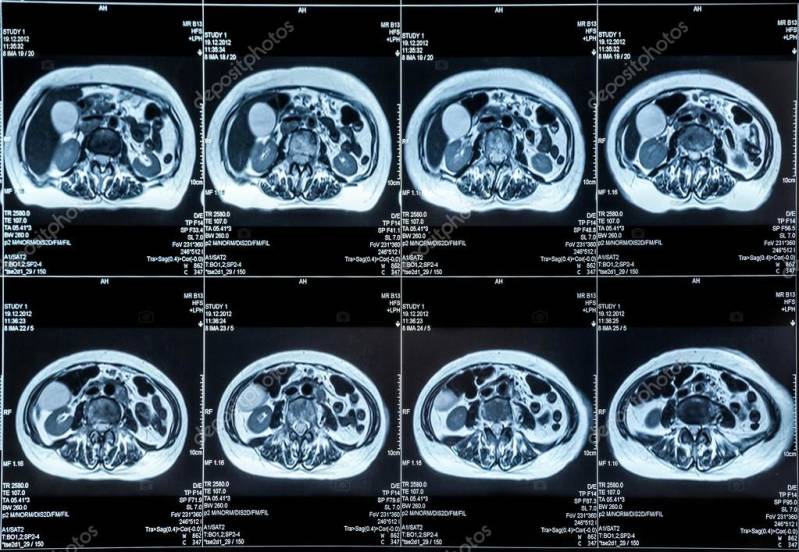

Enkele beelden van een MRI-scan van de buikorganen.

Een mens bestaat voor 63% uit waterstofatomen. Middenin zo'n waterstofatoom zit één proton. Protonen zijn ontzettend gevoelig voor magnetische velden. Wanneer een proton wordt aangetrokken door een magneet, richt het zich tot deze magneet. Wanneer een MRI scanner wordt gebruikt, richten de protonen zich dus tot de magneet van de scanner. Deze situatie wordt 'spin-up' genoemd. Onder invloed van fotonen, een soort elektromagnetische dragers gestuurd door radiofrequentiespoel, verandert deze situatie in een 'spin-down' situatie. Wanneer de radiofrequentiespoel wordt uitgezet, valt het proton vanzelf weer terug naar de oude situatie. Bij dit terugvallen komt er een zogenaamde 'dipool ' straling  vrij. De dipool straling wordt opgevangen in de scanner. Met deze straling kan met een computer een beeld worden gevormd van de binnenkant van het lichaam. Het is alsof er een dwarsdoorsnede van het lichaam wordt gemaakt. Het is zelfs mogelijk om dwarsdoorsnedes van organen te bekijken. Dit geeft een gedetailleerd beeld van de binnenkant van een persoon. Met dit gedetailleerde beeld kan door een arts een diagnose worden gesteld. De MRI-scan is dus een belangrijk medisch apparaat.

Tijdens de MRI-scan ligt de patiënt op een tafel. Deze tafel wordt in een soort tunnel geschoven. Tijdens het onderzoek moet de patiënt zo stil mogelijk liggen, dit omdat er dan een zo duidelijk mogelijk beeld ontstaat. Meestal duurt een MRI-scan tussen de 30 en de 90 minuten.